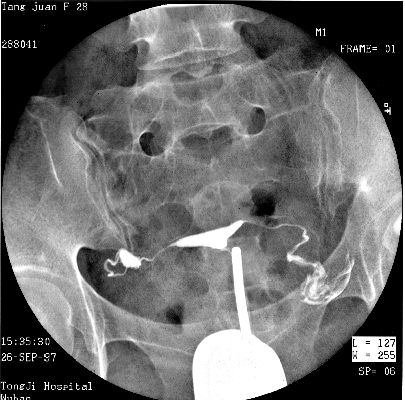

照片名称:子宫输卵管造影3

照片名称:子宫输卵管造影4